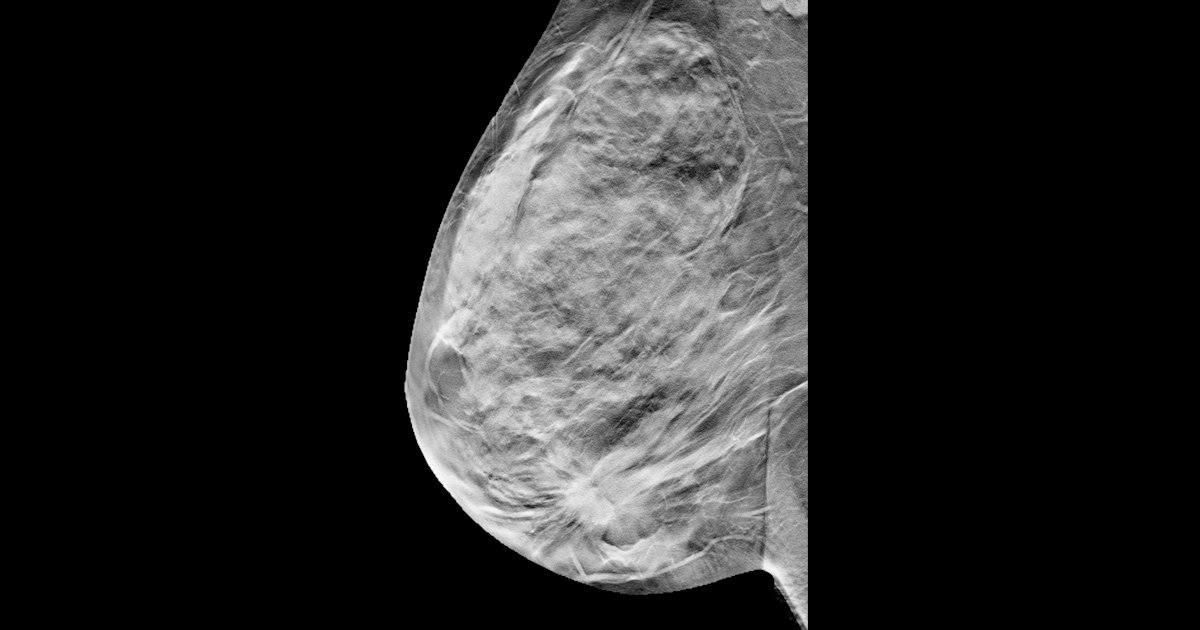

The guidelines outline when the use of PMRT is appropriate based on advances in diagnostics and clinical practice, and reviews best practices for delivering radiation after breast removal surgery, the organizations said.

The document provides information on appropriate target volumes, dosing, and treatment techniques. In addition, authors review treatment approaches aimed at reducing side effects and improving outcomes, including advances in radiation techniques, less invasive axillary surgery, and tailored systemic therapies.